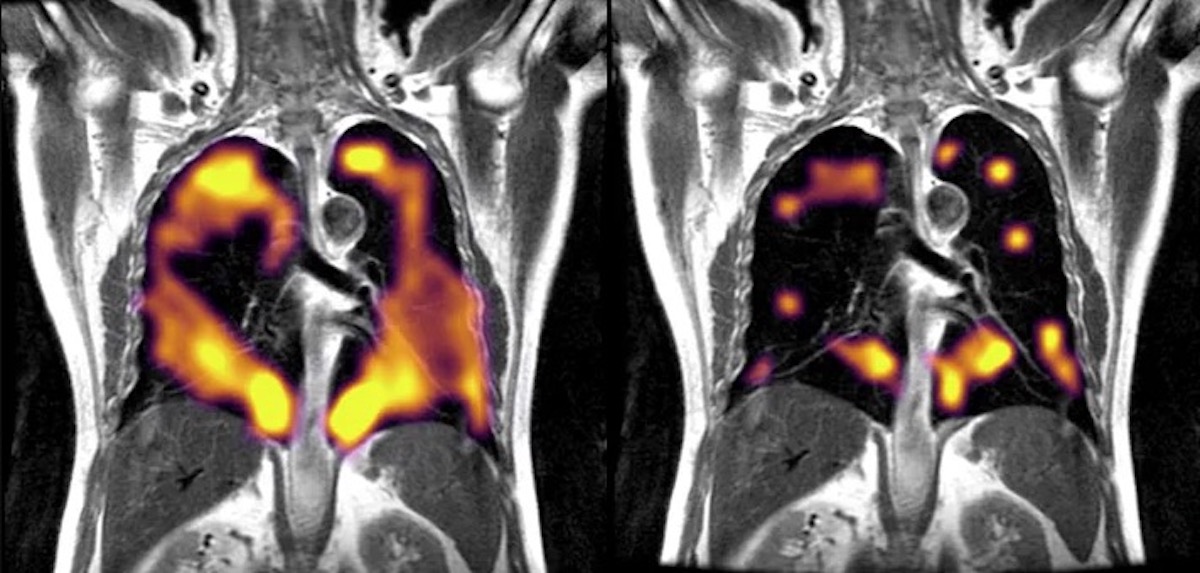

Read moreDetailsChronic obstructive pulmonary disease, better known as COPD, is one of the leading causes of disabilities and death in the country. Over 15 million Americans have been diagnosed with COPD,...